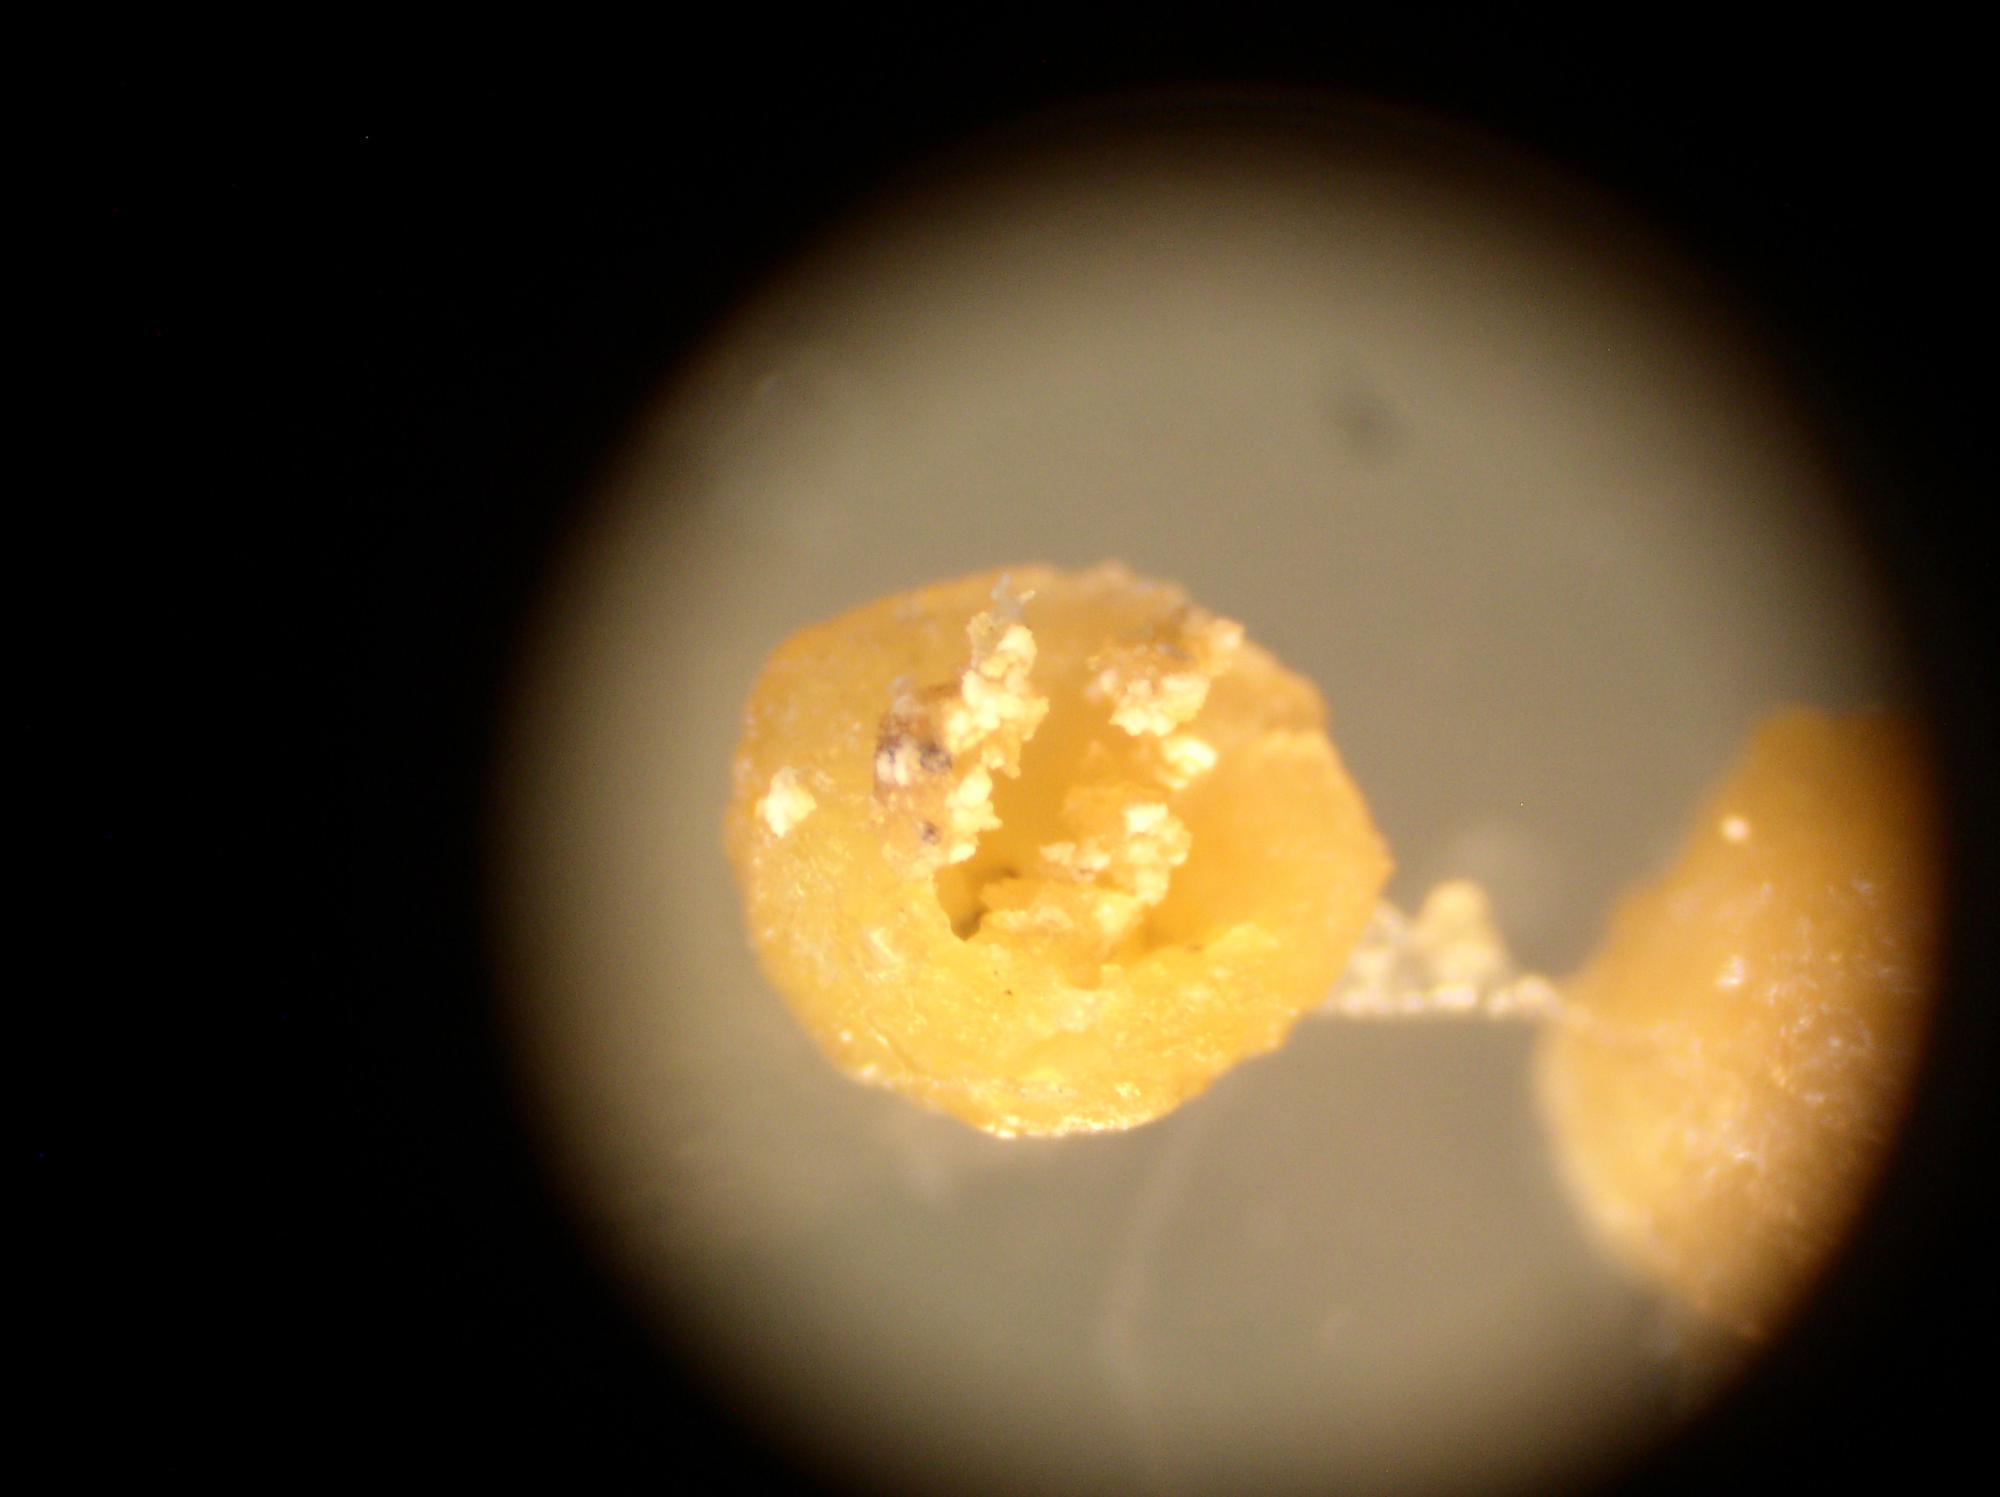

Вот фото, которые удалось сделать дома.

На фото:

1,2,6 - целые капсулы.

Они блестящие, покрыты некой плёнкой.

3-5 - разрезанные капсулы.

Внутренняя структура нопоминает мокрый хлебный мякиш.

В этом "мякише видны чёрные включения, как кусочки грязи.

больше похоже на жировики. При большем увеличении не микроскопировали?